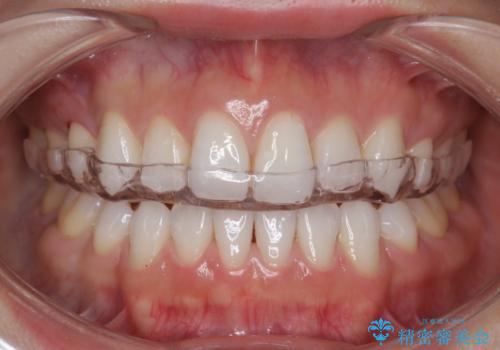

奥歯が欠けた セラミックインレーでの修復後、ナイトガード装着

- 右下の奥歯が欠けたとのことで来院されました。

欠けた部分にはセラミックインレーで修復処置を行い、今後の破折リスクを抑えるためにナイトガードを製作していきます。

食いしばりが強い方はセラミックがまた割れる可能性があるため、予防的にナイトガードを装着することをお勧めします。